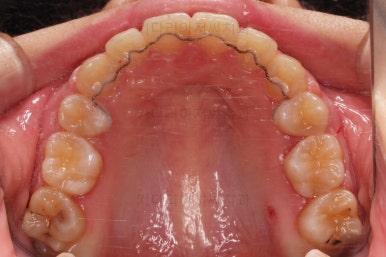

마찬가지로 부산연산동교정치과 초진 시 입안의 모습입니다.

눈에 띄는 것은 윗니 안쪽 치아 하나가 아예 입천장쪽으로 나서 매우 삐뚤어요.

저렇게 삼각혁으로 배치되어 있는 치아는 셋 중 하나는 꼭 썩어요.

셋 사이에 음식물이 잘 끼고 양치가 힘들기 때문이죠.

아래 앞니도 삐뚤한 편이었고 아래 앞니가 불쑥 위로 올라와 있어서 이를 악 다물면 위아래 앞니가 많이 겹치는 "과개교합" 패턴이 나타나요.

윗니가 전반적으로 아랫니보다 앞에 나와 있어서 2급 부정교합에 윗니만 튀어나온 양상이고 이 때문에 윗니 앞니가 다치고 부러졌따가 떼운 흔적이 보이네요.